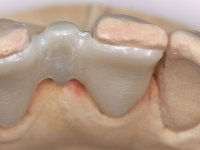

Go to lab case >

In the dental lab, a Maryland bridge with a zirconia framework veneered with a feldspathic ceramic was built. The wings internal surface also had a very thin coating of a zirconia adhesive to allow its bonding to the abutments enamel. This Maryland bridge tried to join the mechanical strength of the framework, to the bonding of the ceramic to the enamel, and to the aesthetics’ of the zirconia’s veneering with a feldspathic ceramic.